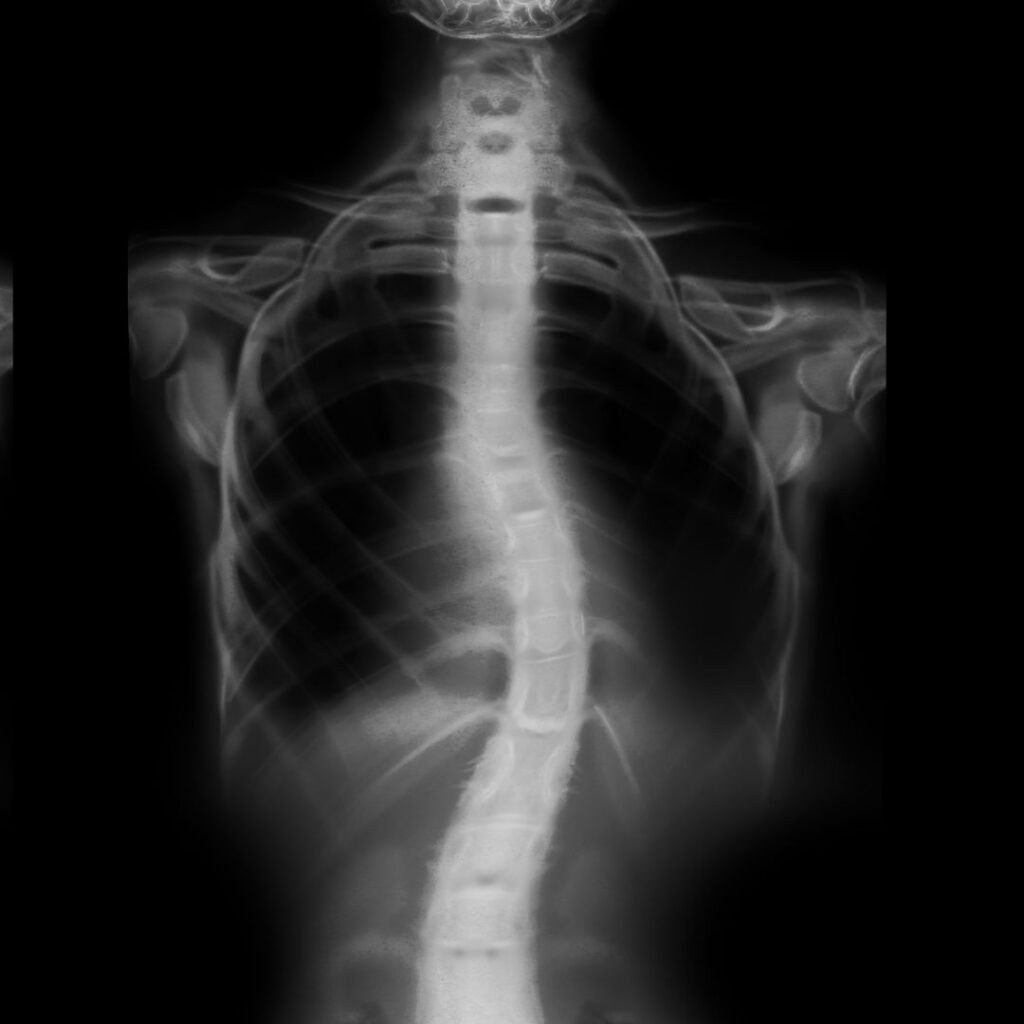

As someone struggling with scoliosis, the primary concern is always who to see for the right scoliosis treatment. In Toronto, when you search for a scoliosis specialist, a list of specialists and doctors appears, but selecting the right one is where most people feel lost. The majority of people are not aware of whom to approach or what to consider before approaching anyone. And since scoliosis is a sensitive problem, reaching the right specialist for the treatment becomes even more important. For scoliosis treatment for children and adults, there are usually different specialists, and there are very few who can assist patients from all age groups.

Firstly, you must understand how severe the problem is and the age of the patient. Treatment options for mild scoliosis vary from moderate to severe cases. Once you have got the diagnosis and have understood your needs, then search for all the specialists in the town. Make a list of the top specialists and research about each one of them. Check how experienced the teams are, their experience, and, if possible, try connecting with any patients who have an ongoing treatment or have already got the treatment from them. This research will provide huge clarity and help you better figure out whom to approach. And to whomever you consult, you must ensure they have a comprehensive approach to treatment.